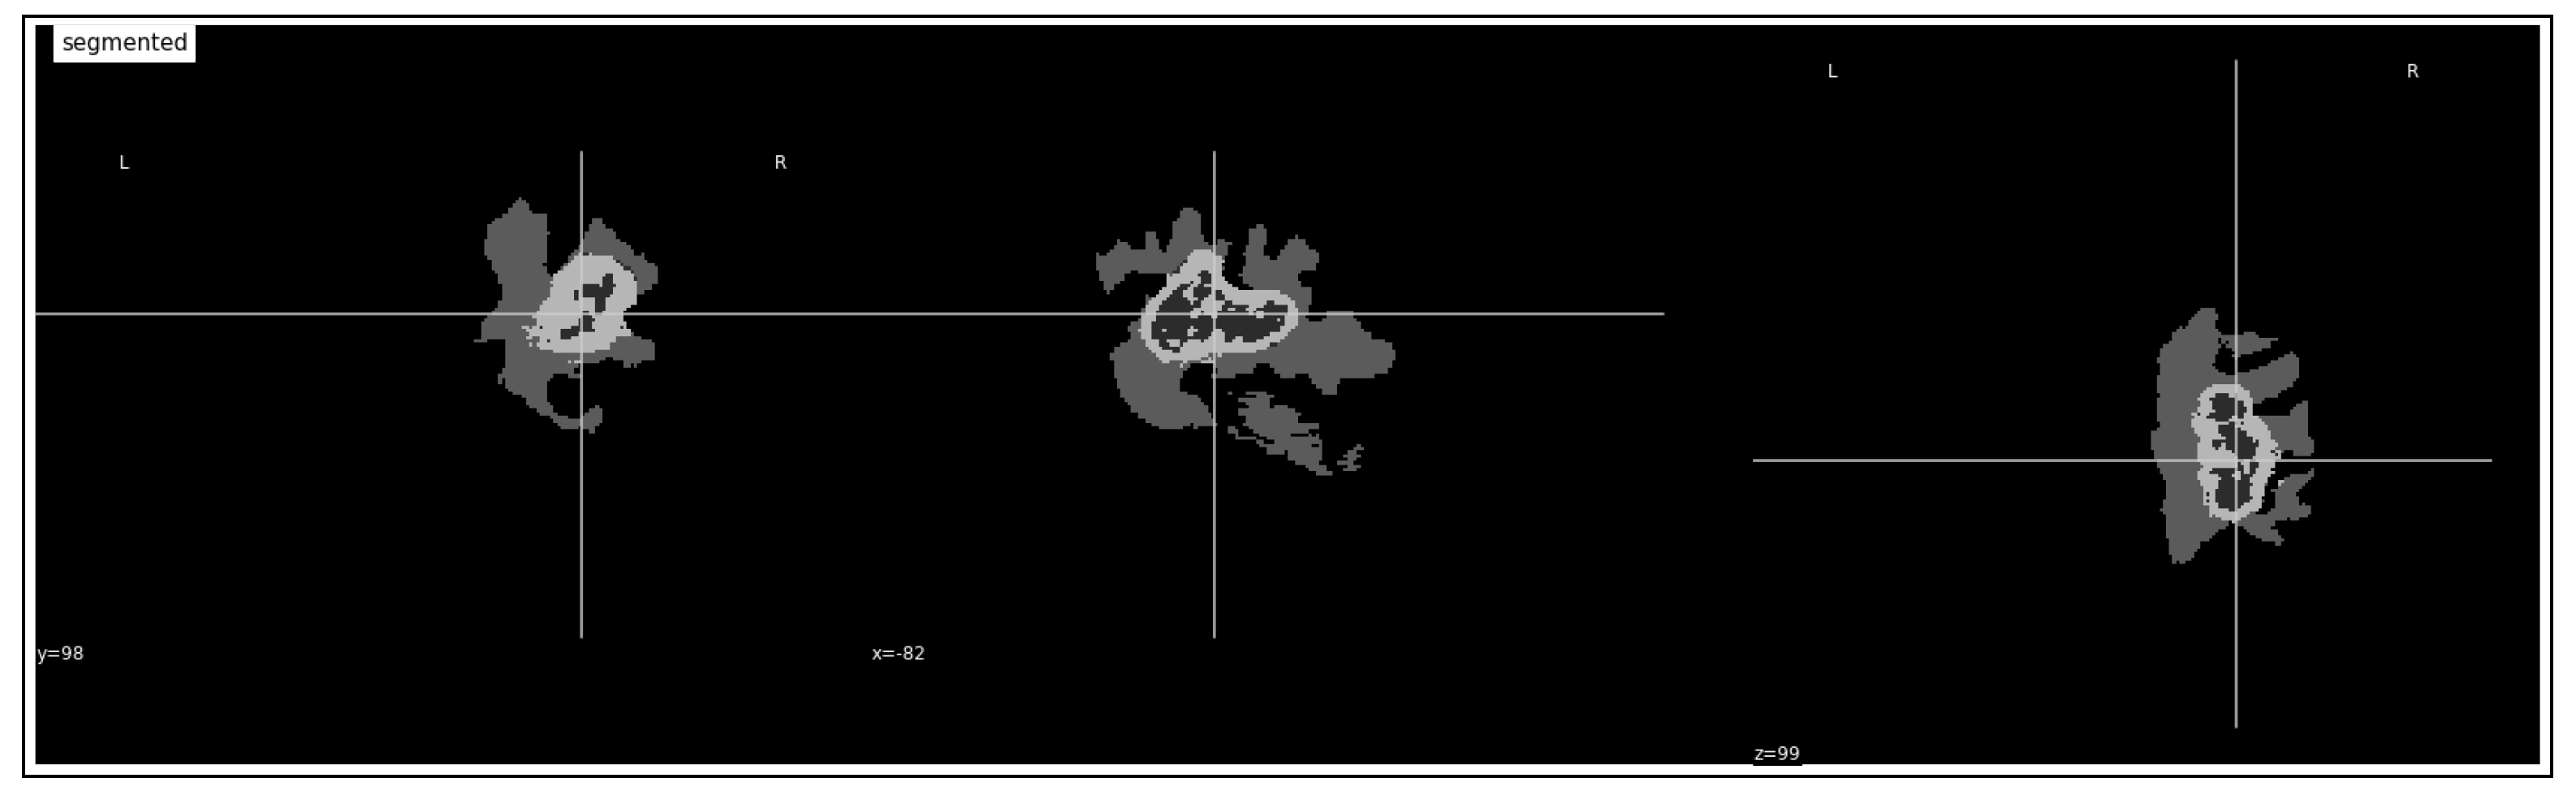

3.3. Tumor Volume Computation

4.3.1. Tumor Identification